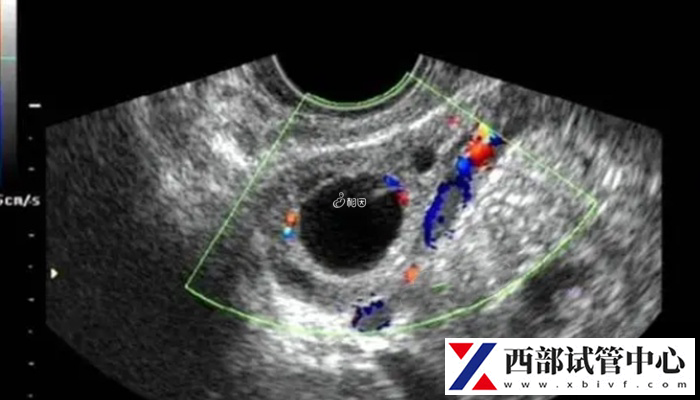

控制性超排卵与卵泡监测

为了提高妊娠率,目前在试管婴儿-ET技术中,多采用控制性超排卵法,即选用人类促性腺激素,增强与改善卵巢功能,使一次周期能有多个卵泡发育,回收多个卵供受精。以获得较多供移植的胚胎。但促超排卵法有时会有卵泡早熟、质量差的情况。